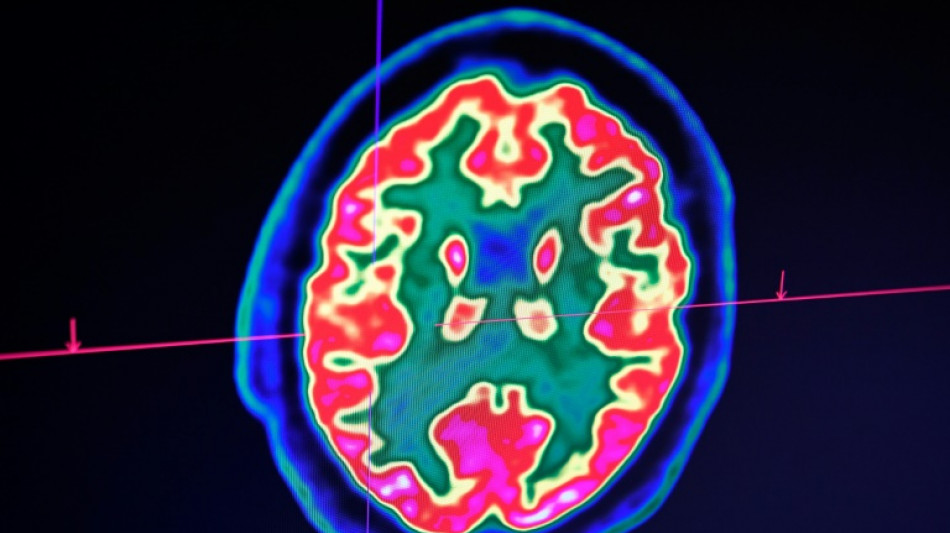

Cancer du cerveau: la guérison d'un enfant ouvre de grands espoirs pour la recherche / Photo: Fred TANNEAU - AFP

Rare mais fatal, le gliome infiltrant du tronc cérébral est l'une des formes les plus redoutables des cancers du cerveau pédiatriques. Un enfant, pourtant, semble défier les statistiques: sa guérison, unique au monde, suscite aujourd'hui de grands espoirs pour la recherche.

D'emblée, Lucas répond très bien au traitement. "Au fil des IRM, j'ai vu la tumeur complètement disparaître", raconte le Dr Grill, qui n'ose, malgré ces résultats miraculeux, décider d'arrêter le médicament. Jusqu'à ce qu'il comprenne, il y a un an et demi, que l'enfant avait lui-même cessé de le prendre.